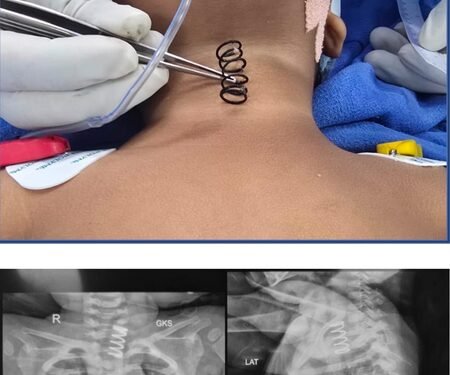

The metal spring stuck in the oesophagus, also known as the food pipe, was successfully removed after an endoscopic surgery, AIIMS said in an official statement.

“During the examination, an X-ray revealed a large metal spring lodged in the upper part of the child’s oesophagus,” AIIMS said, “with ulcerations extending along the mucosa”.

“The spring was stuck on the upper part of the food pipe. And the thickness of the spring was much more than the normal spring, which we see in our pens. It was approximately half an inch wide and at least 1.5 to 2 inches long,” Professor Dr. Vishesh Jain, from the Paediatric Surgery Department, told IANS.

Jain and his team used advanced endoscopic techniques in the operating room. The spring was carefully rotated and removed, preventing any perforation, the statement said.